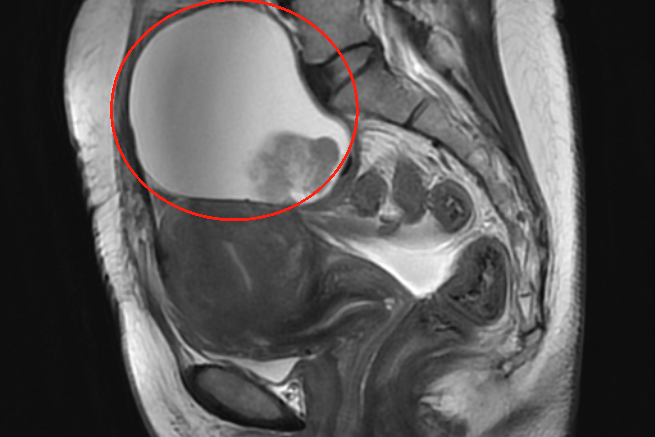

直到八月的一天,手心不经意间抚过下腹,一块硬邦邦的东西清晰可触。她心里咯噔一下。第二天一早就赶往当地医院。影像检查显示:包块已长至约103×80mm,如一个西柚大小。

入院后,增强CT、肿瘤标志物检查等一系列检查结果陆续回报,高度提示卵巢恶性肿瘤或交界性肿瘤可能。

三个多小时后,肿瘤被完整切除。术中冰冻病理结果回报:透明细胞癌。